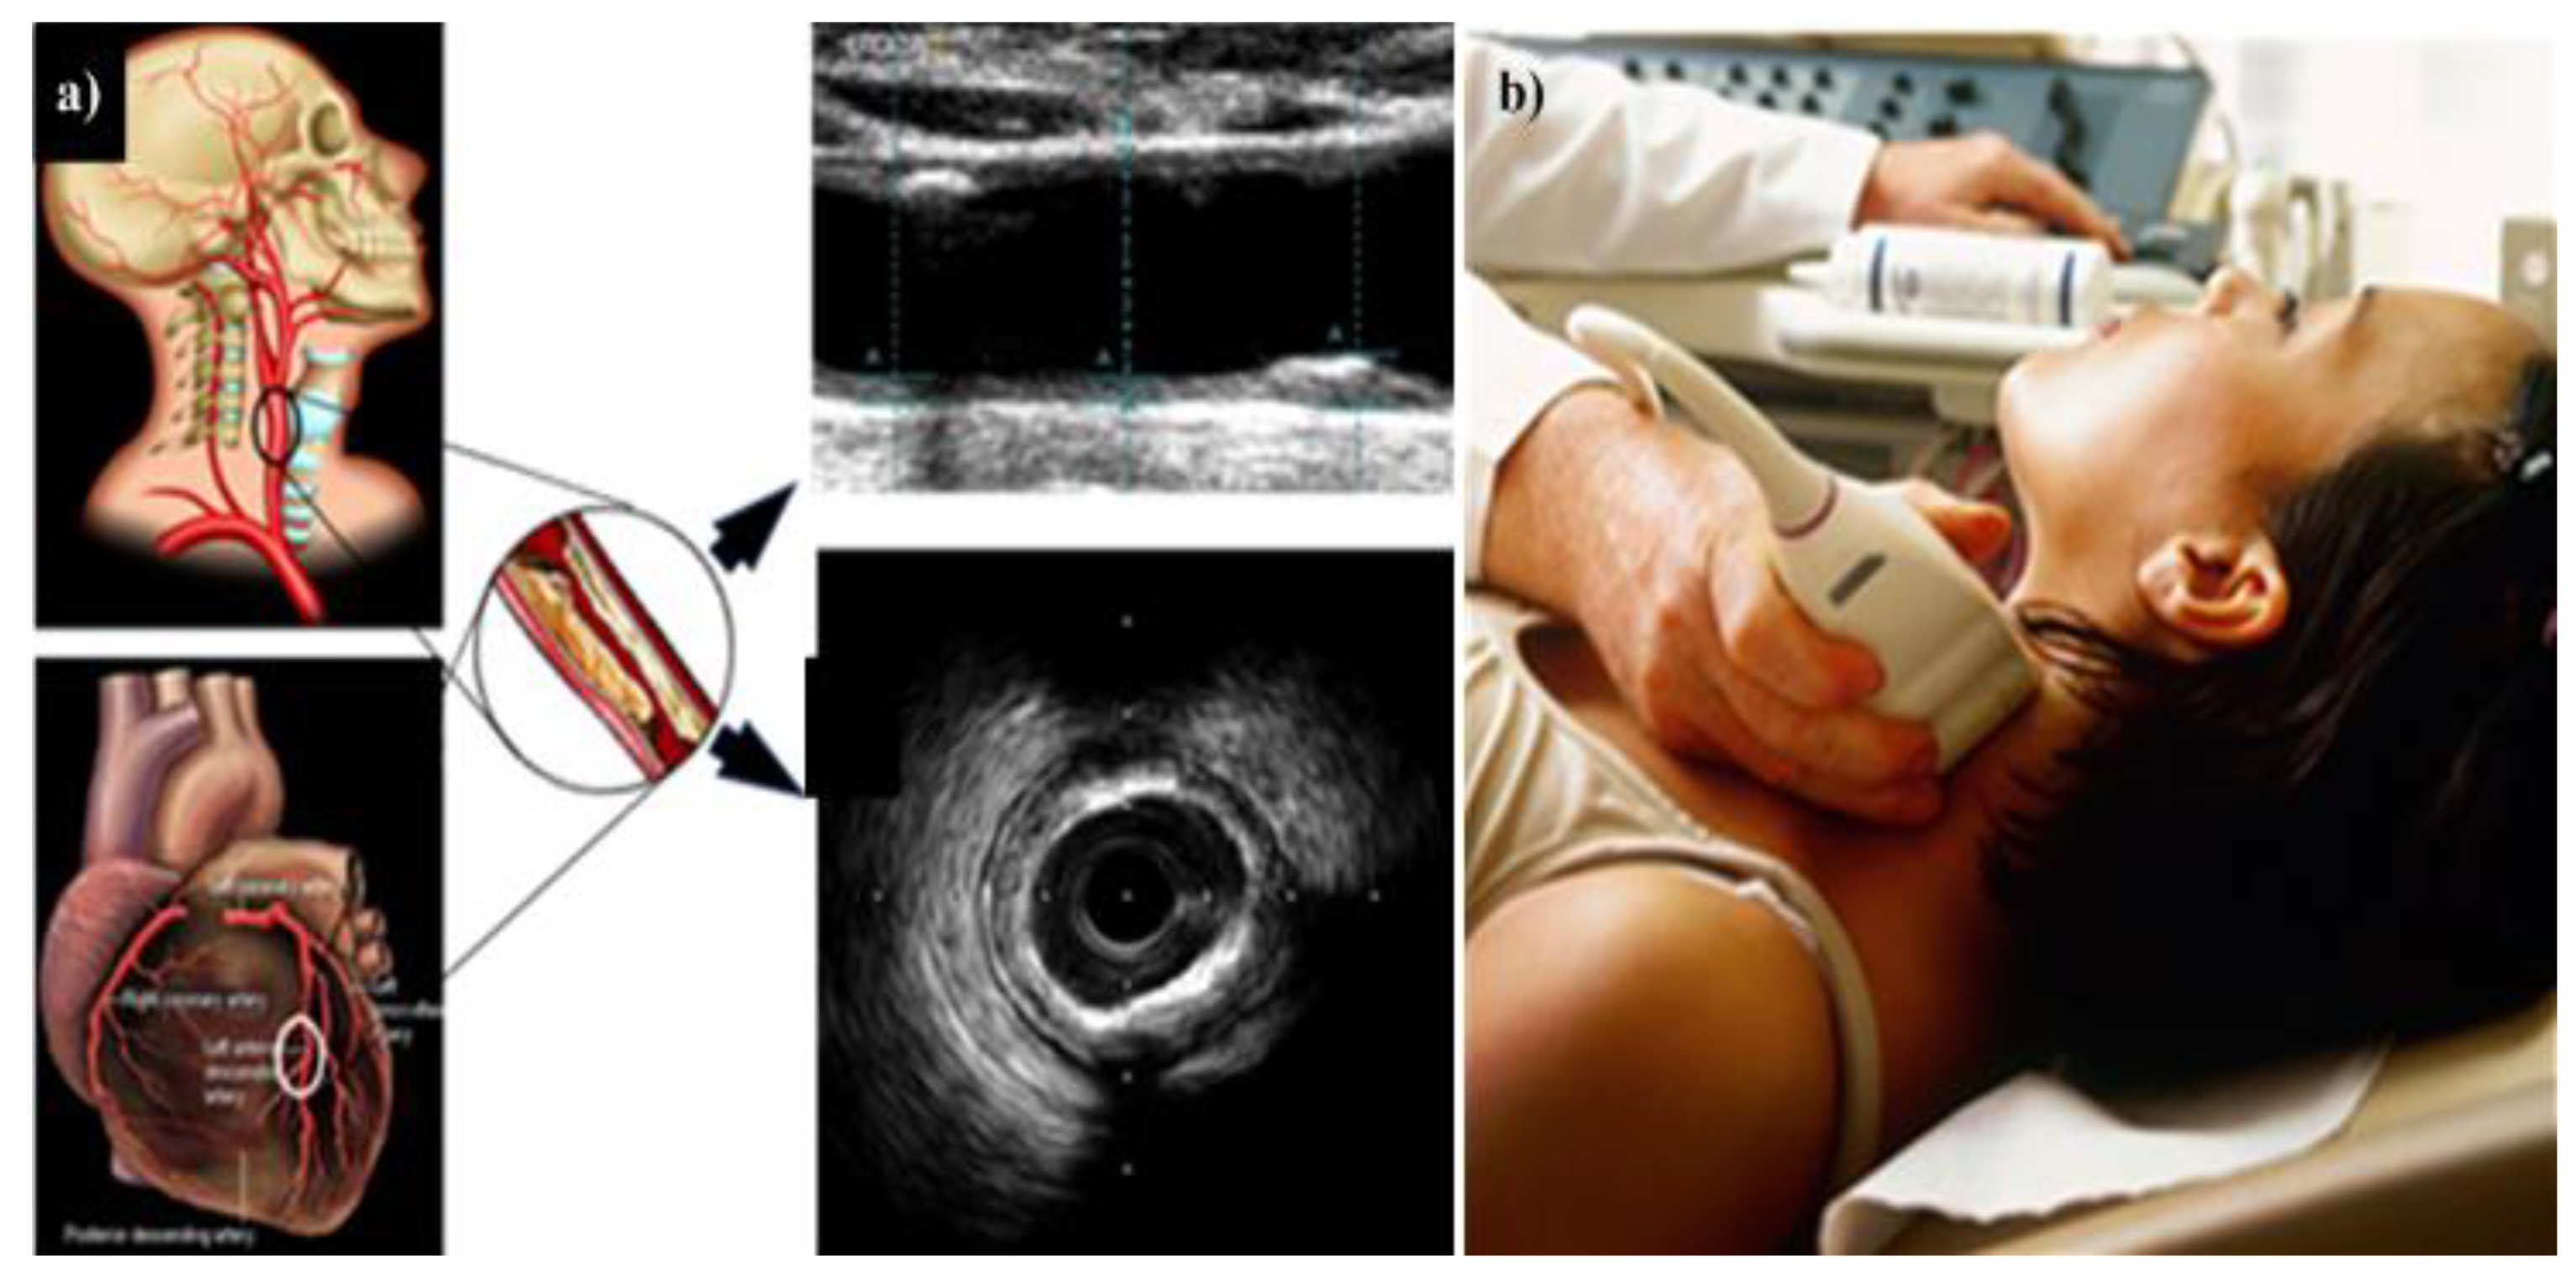

4. Carotid Imaging for CVD Risk Assessment in DR Patients

4.2. Carotid Artery Disease—A Surrogate of Coronary Artery Disease or Cardiovascular Disease